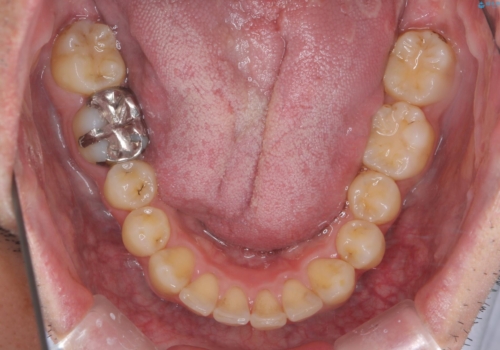

出っ歯と歯のねじれ 非抜歯で 30代男性

奥歯のかみ合わせを特に変えず、前歯の並びを整える治療をおこないました。

奥歯のかみ合わせは1本分ずれているとはいえ、1歯対2歯の交互のかみ合わせになっているため、そのままにしてもそこまで大きなデメリットはありません。

右上のかみ合わせをそのままにするため、上下の正中は合わない仕上がりとなります。

今回は右のかみ合わせはそのままにしました。左は特に初めから問題ない状態でした。

右のかみ合わせを変えず部分矯正にしたことによって、治療が短期間で済み、また、ワイヤーでなくインビザラインで治療が可能、歯も抜かなくて済むなどメリットの多い方法であるといえます。